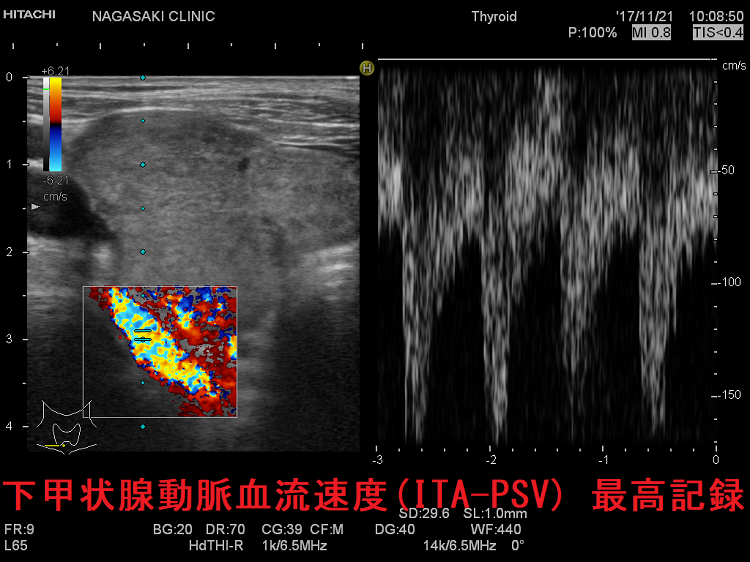

下甲状腺動脈血流速度(ITA-PSV)の最高値

下甲状腺動脈血流速度(ITA-PSV) 最高記録

長崎甲状腺クリニック(大阪)での下甲状腺動脈収縮期最大血流速度(ITA-PSV) 最高記録は、計測限界を突破しています。写真の如く、170cm/sを超えていて、それ以上測れません。難治性T3優位型バセドウ病で、治療抵抗性です。

下甲状腺動脈血流速度(ITA-PSV )最高値

長崎甲状腺クリニック(大阪)での下甲状腺動脈収縮期最大血流速度(ITA-PSV) 最高記録が更新されました、計測限界を突破し、200cm/sを超えています。